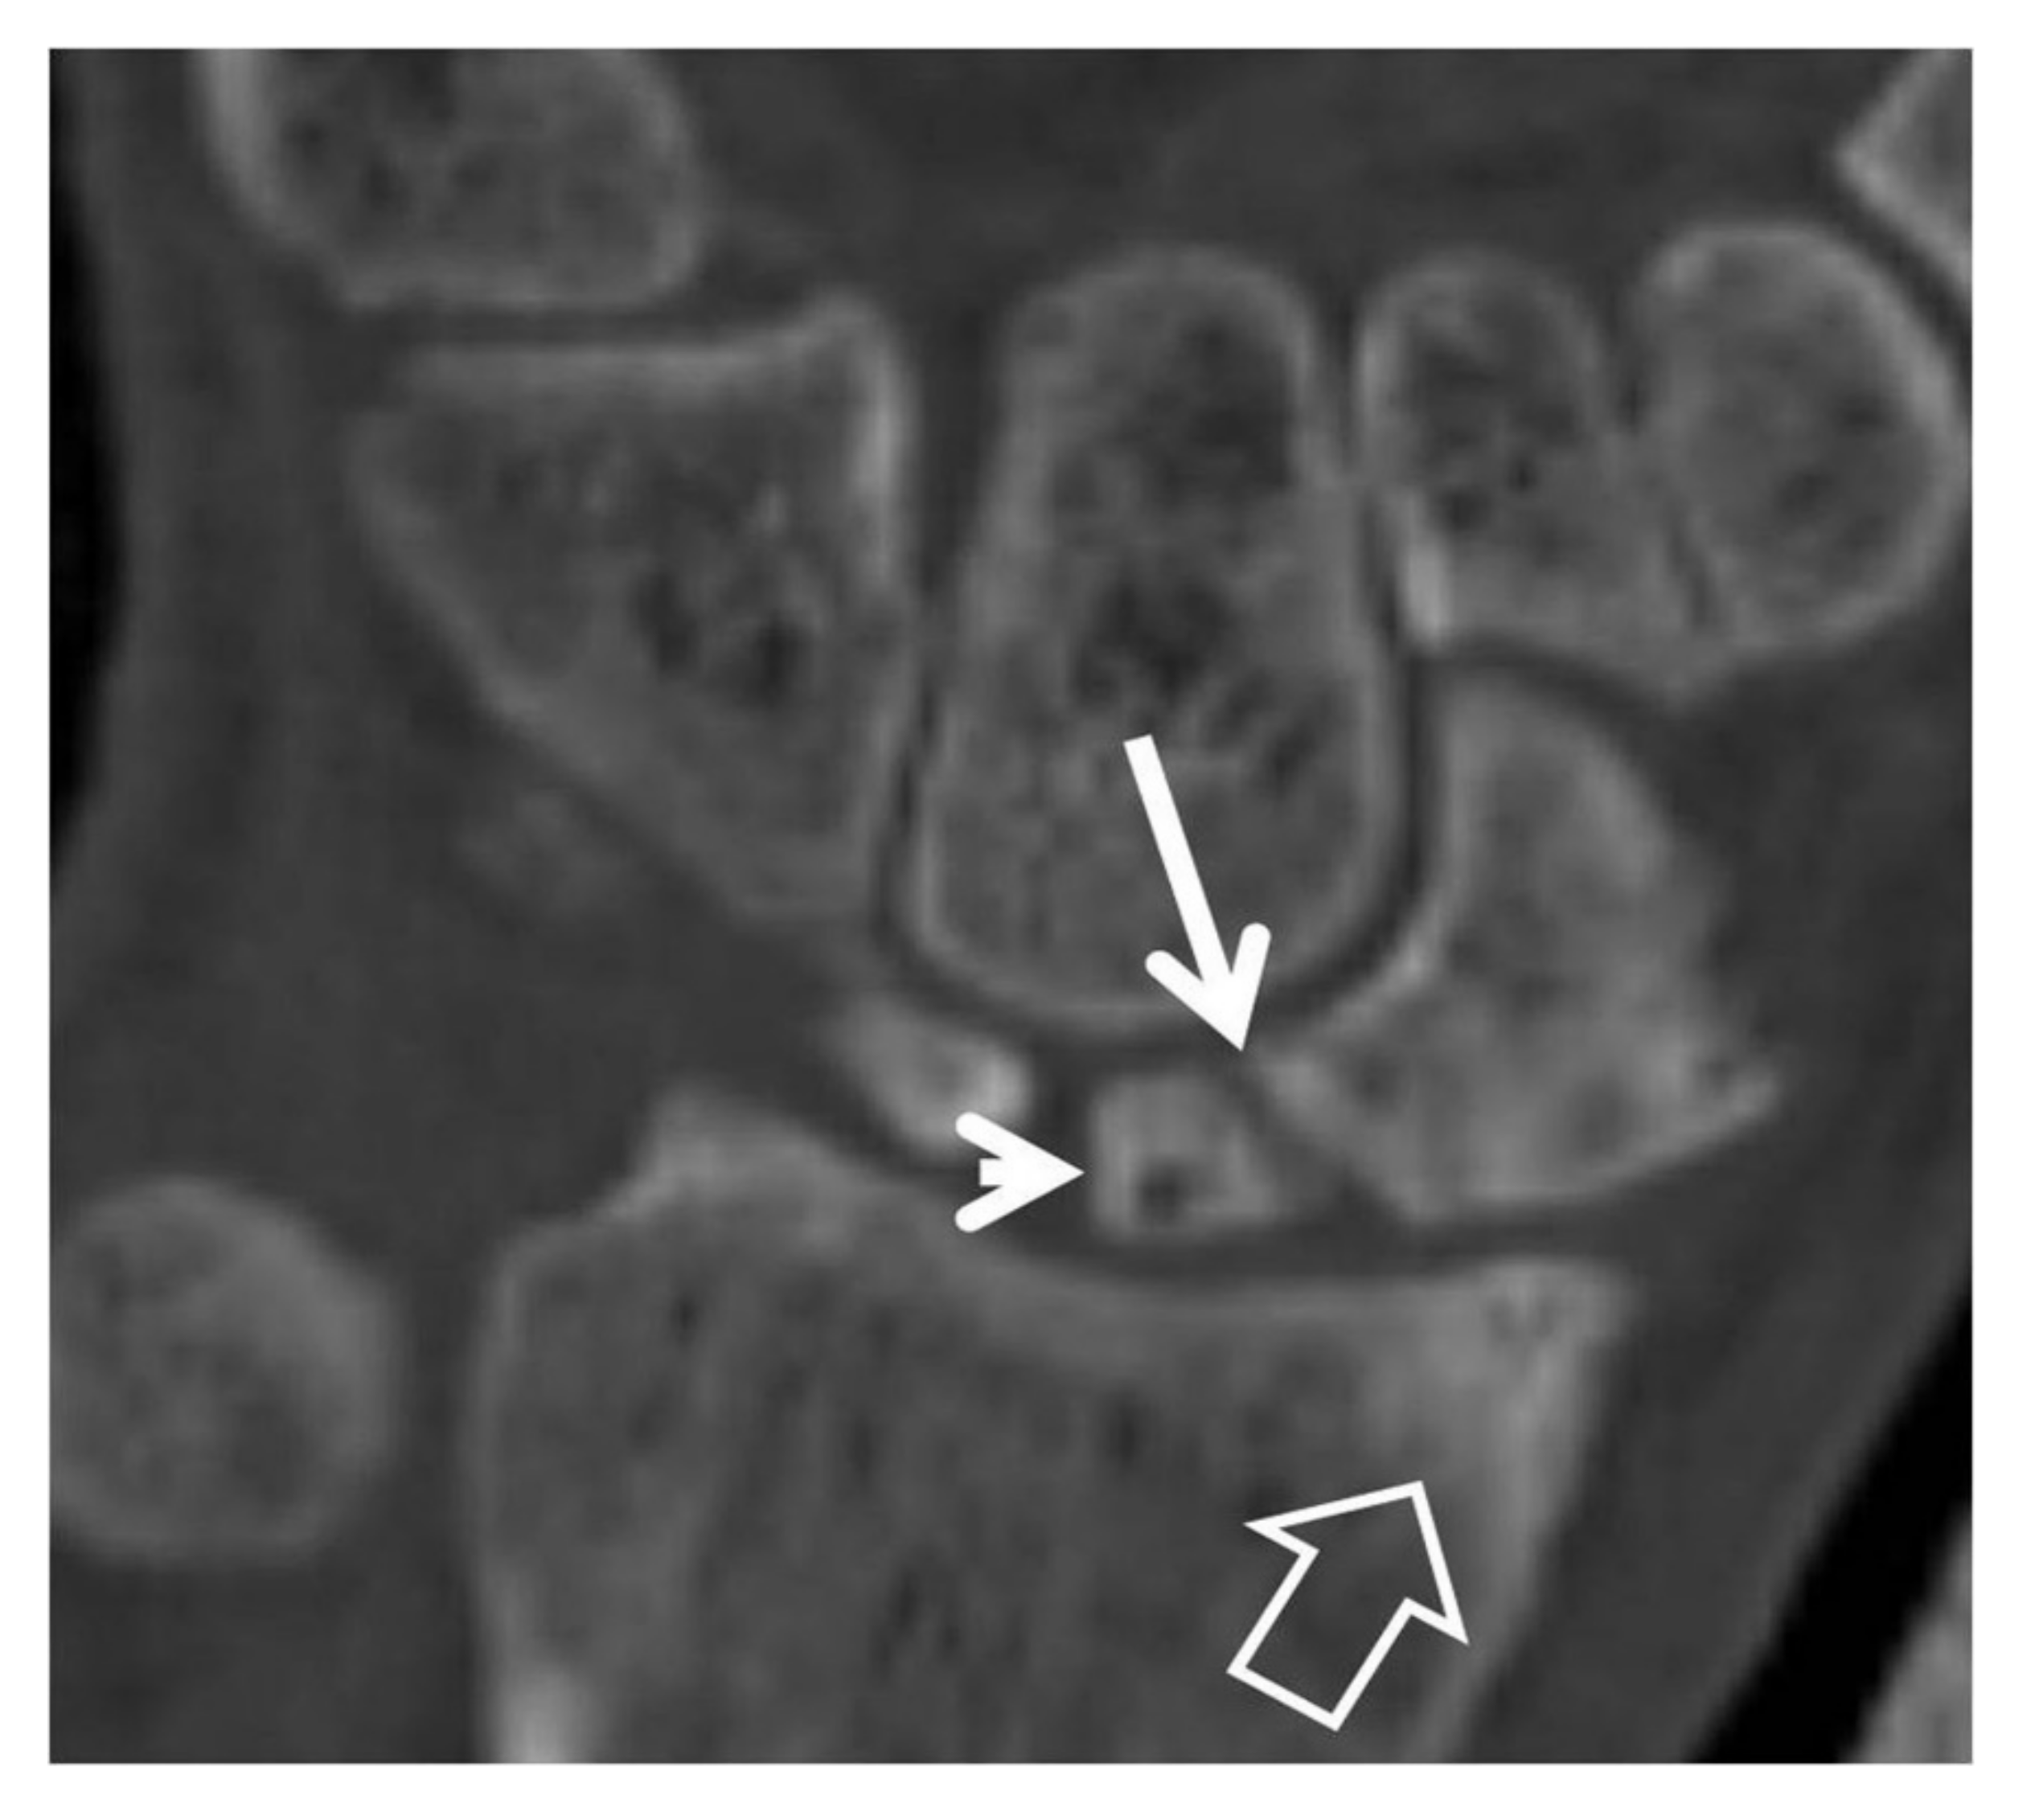

In SNAC, one of the main MDCT findings is the exact location of the non-union scaphoid fracture (Figure 5b, Figure 6a, Figure 7 and Figure 9). This location is important for the prognosis of the disease as a non-union fracture at the proximal third of the scaphoid has a higher chance of dorsal flexion of the lunate and is thus more prone to extensive cartilage degeneration.

Figure 9.

A 42-year-old male patient with pseudarthrosis following previous scaphoid fracture. Coronal CT reconstruction showing the fracture non-union (arrow), the proximal pole osteosclerosis with cyst formation (arrowhead) and the subarticular osteosclerosis of the radial styloid (open arrow) in keeping with early osteoarthritis.